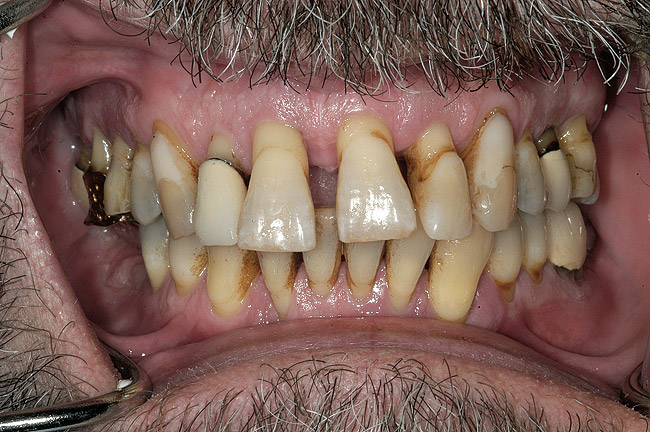

Un pacient în vârstă de 53 ani s-a prezentat cu îngrijorarea majoră privind aspectul, sensibilitatea şi mobilitatea dinţilor săi (fig. 1). El a răspuns pozitiv la chestionarul dentar referitor la sângerarea gingiei, dinţi dureroşi, sensibilitate la temperatură, gustul sau mirosul neplăcut al cavităţii orale, bruxism şi pierderea dinţilor.

La examinare s-au obiectivat: dinamică labială maxilară crescută, cu afişarea în repaus a 3-4mm din incisivi. La zâmbetul total, marginile gingivale libere nu erau vizibile, datorită recesiunii, dar 2-4mm din structura radiculară era vizibilă dincolo de joncţiunea smalţ-cement (CEJ) la toţi dinţii superiori. Festonul ţesutului moale era apropiat de normal, însă părea neatractiv datorită gradului mare de recesie şi a pierderii papilei. În regiunea frontală inferioară s-a remarcat asimetria orizontală (fig. 2).

Obiective terapeutice

Consideraţiile privind managementul riscului şi planul de tratament au fost elaborate utilizându-se o abordare sistematică. Tratamentul ar fi redus riscul biomecanic prin eliminarea dinţilor compromişi structural (fig. 3,4), cu diminuarea concomitentă a riscului funcţional prin crearea unei ocluzii în armonie cu articulaţiile. În plus, tratamentul ar fi redus riscul parodontal prin îndepărtarea dinţilor irecuperabili, cu implicare parodontală, (fig. 5) şi ar fi îmbunătăţit estetica prin ridicarea cu 3mm a planului ocluzal pentru a minimiza expunerea gingivală şi a rădăcinilor.5-8